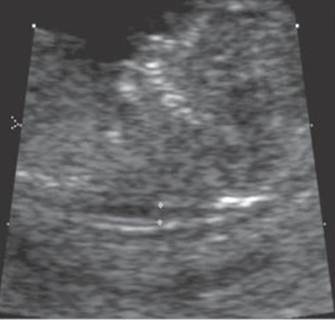

Anterior uterine fibroid